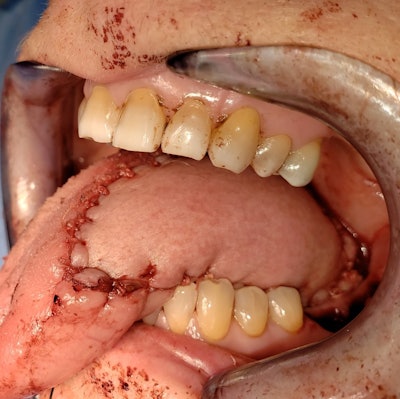

The submental artery flap was first described in 1993.1 It is based off the submental artery and vein, which are branches of the facial vessels. It is harvested at the time of the neck dissection, as the pedicle is dissected off the submandibular gland and is generally harvested in 30 to 60 minutes. The resulting submental defect can be closed primarily with minimal additional elevation of the neck flaps. It is ideal for defects of the floor of mouth and lateral tongue but can also be used for the palate and skin of the face. While it is generally contraindicated in the setting of bulky level I adenopathy, smaller nodes of concern are easily dissected out of the flap pedicle with no effect on oncologic outcome.2 Reconstructive outcomes compare favorably with the radial forearm free flap (Figure 1).

Figure 1a. Lateral tongue defect reconstructed with a radial forearm free flap.

Figure 1b. Comparable defect with a submental island flap.